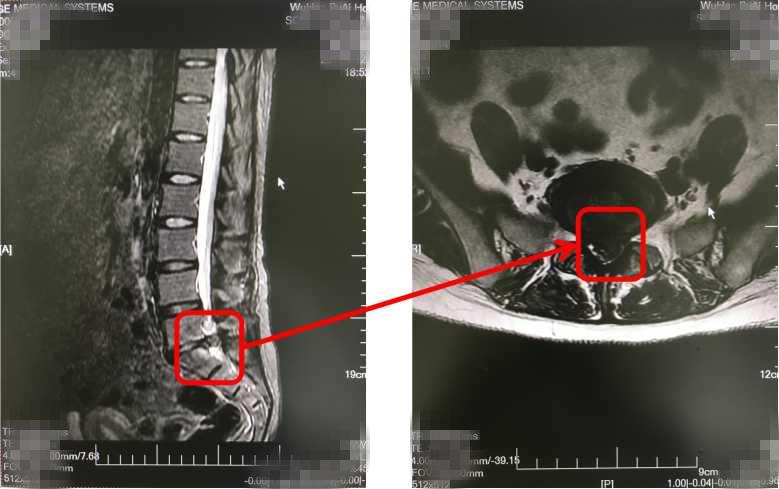

然而,休息了几天,却发现两条腿又痛又麻,而且这几天还连续便秘、肚子涨得难受。无奈之下,只好去医院进行检查,结果通过腹部B超等检查,并没有发现肠胃有什么问题,却在照腹部DR检查的时候发现,黄女士的腰椎间盘突出压迫到马尾神经,因而才会导致她下肢麻木疼痛、排便困难等症状,后经手术治疗,黄女士康复出院。

其实,如果腰椎间盘突出压迫到位于腰椎第二节以下的神经根,就会引发马尾神经损害,出现神经性功能障碍,从而导致便秘或大小便功能障碍等症状。

因为我们的肠道受交感神经和副交感神经所支配,如果腰椎椎体发生错位,压迫了位于椎体前面的交感神经节,导致交感神经和副交感神经出现紊乱,从而引发肠道的功能受到干扰,出现便秘症状。